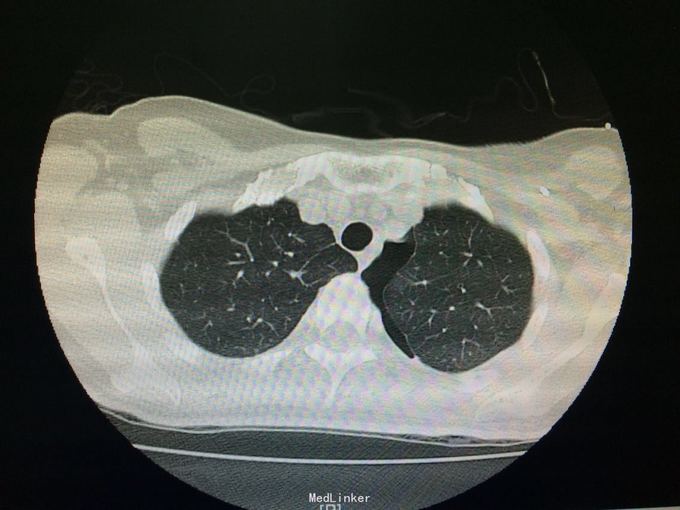

随访:夹管24h后查胸部CT示:左肺下叶炎症、左侧胸腔少量积气、积液。 讨论:该患者是否需要继续闭式引流排气,是否需继续抗生素治疗?